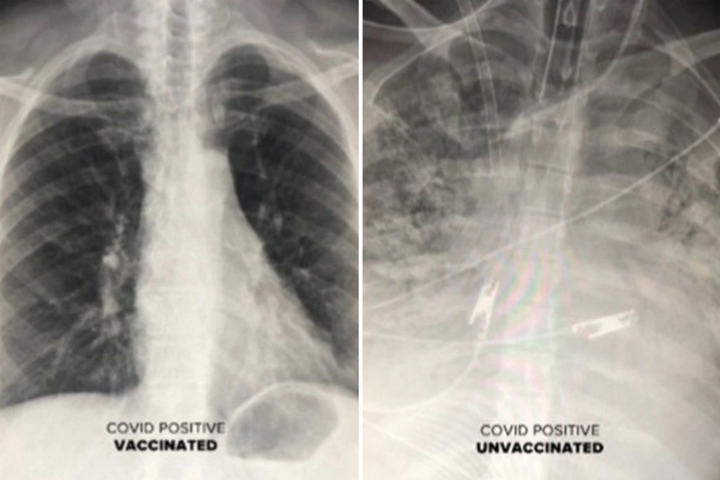

Bác sĩ Durrani cho biết, phim chụp phổi của những bệnh nhân COVID-19 từng được tiêm chủng cho thấy không khí lưu thông nhiều hơn. Trên hình, phần lớn phổi có màu đen, nghĩa là có rất ít hoặc không có tổn thương nào.

Ngược lại, phim chụp của một người không được tiêm chủng cho thấy phổi bị tắc nghẽn, hạn chế lưu lượng oxy đi khắp cơ thể.

Phim chụp phổi của người đã tiêm vaccine (trái) không bị trắng xóa như người chưa tiêm vaccine.

Tiến sĩ Durrani cho biết: “Nếu một người đã được tiêm vaccine vẫn nhiễm COVID-19 (nhiễm trùng đột phá), họ có thể bị khó thở. Dù những ca nhiễm trùng đột phá dẫn đến viêm phổi, kết quả chụp CT của họ vẫn không tệ như bệnh nhân chưa được chủng ngừa”.

Với hình ảnh cho thấy sự tàn phá mà virus SARS-CoV-2 có thể gây ra trong phổi, Tiến sĩ Durrani khẳng định: “vaccine đang hoạt động cực kỳ hiệu quả và ngăn không cho virus gây ra viêm phổi hoặc xâm nhập vào phổi.